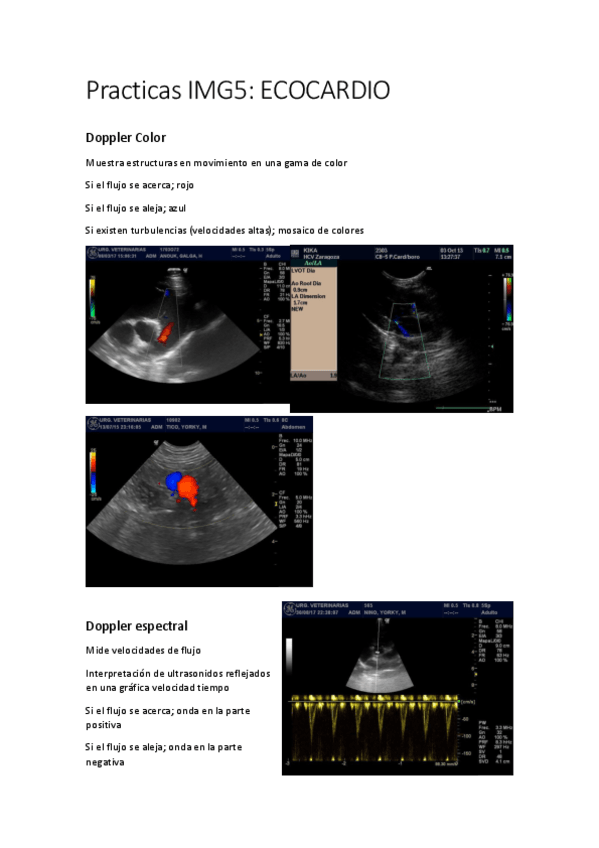

3.2.-ECOCARDIOGRAFIA.pdf